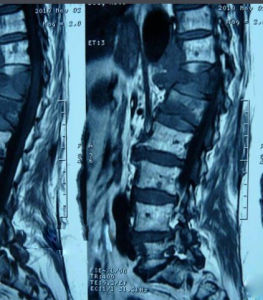

胸腰椎壓縮性骨折多發於下胸段和上腰段。應仔細了解損傷史,患者主訴背痛,不敢活動,可妨礙站立行走。如果壓縮程度較重,後柱的棘突或韌帶有損傷,產生局部後凸畸形,或出現腫脹淤斑。壓痛叩擊痛常見,胸腰椎活動受限。胸腰椎壓縮性骨折大部分為穩定骨折,少有脊髓損傷癱瘓者。診斷

胸腰椎壓縮性骨折 治療